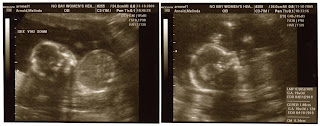

Ok, it's only been, like, 12 weeks since we actually had the 21 week ultrasound and all...better late than never, right?!?! Anyway, here is our little Zoe Emma! I'm actually 33 weeks as I write this post. The weeks are flying by! We've settled in to our rental home here in Little Elm, TX. and the baby's room is pretty much set to go. Last weekend, we went to the medical center where we are having her for the child birth tour. It's the first time that it's really hit me...she's coming and soon! We are so excited:-) After I post this, I'll download some pics of her nursery. I think it turned out way cute...way more pink than I ever thought I'd decorate with but, hey, you gotta love the girlie thing while you can, right?!?!